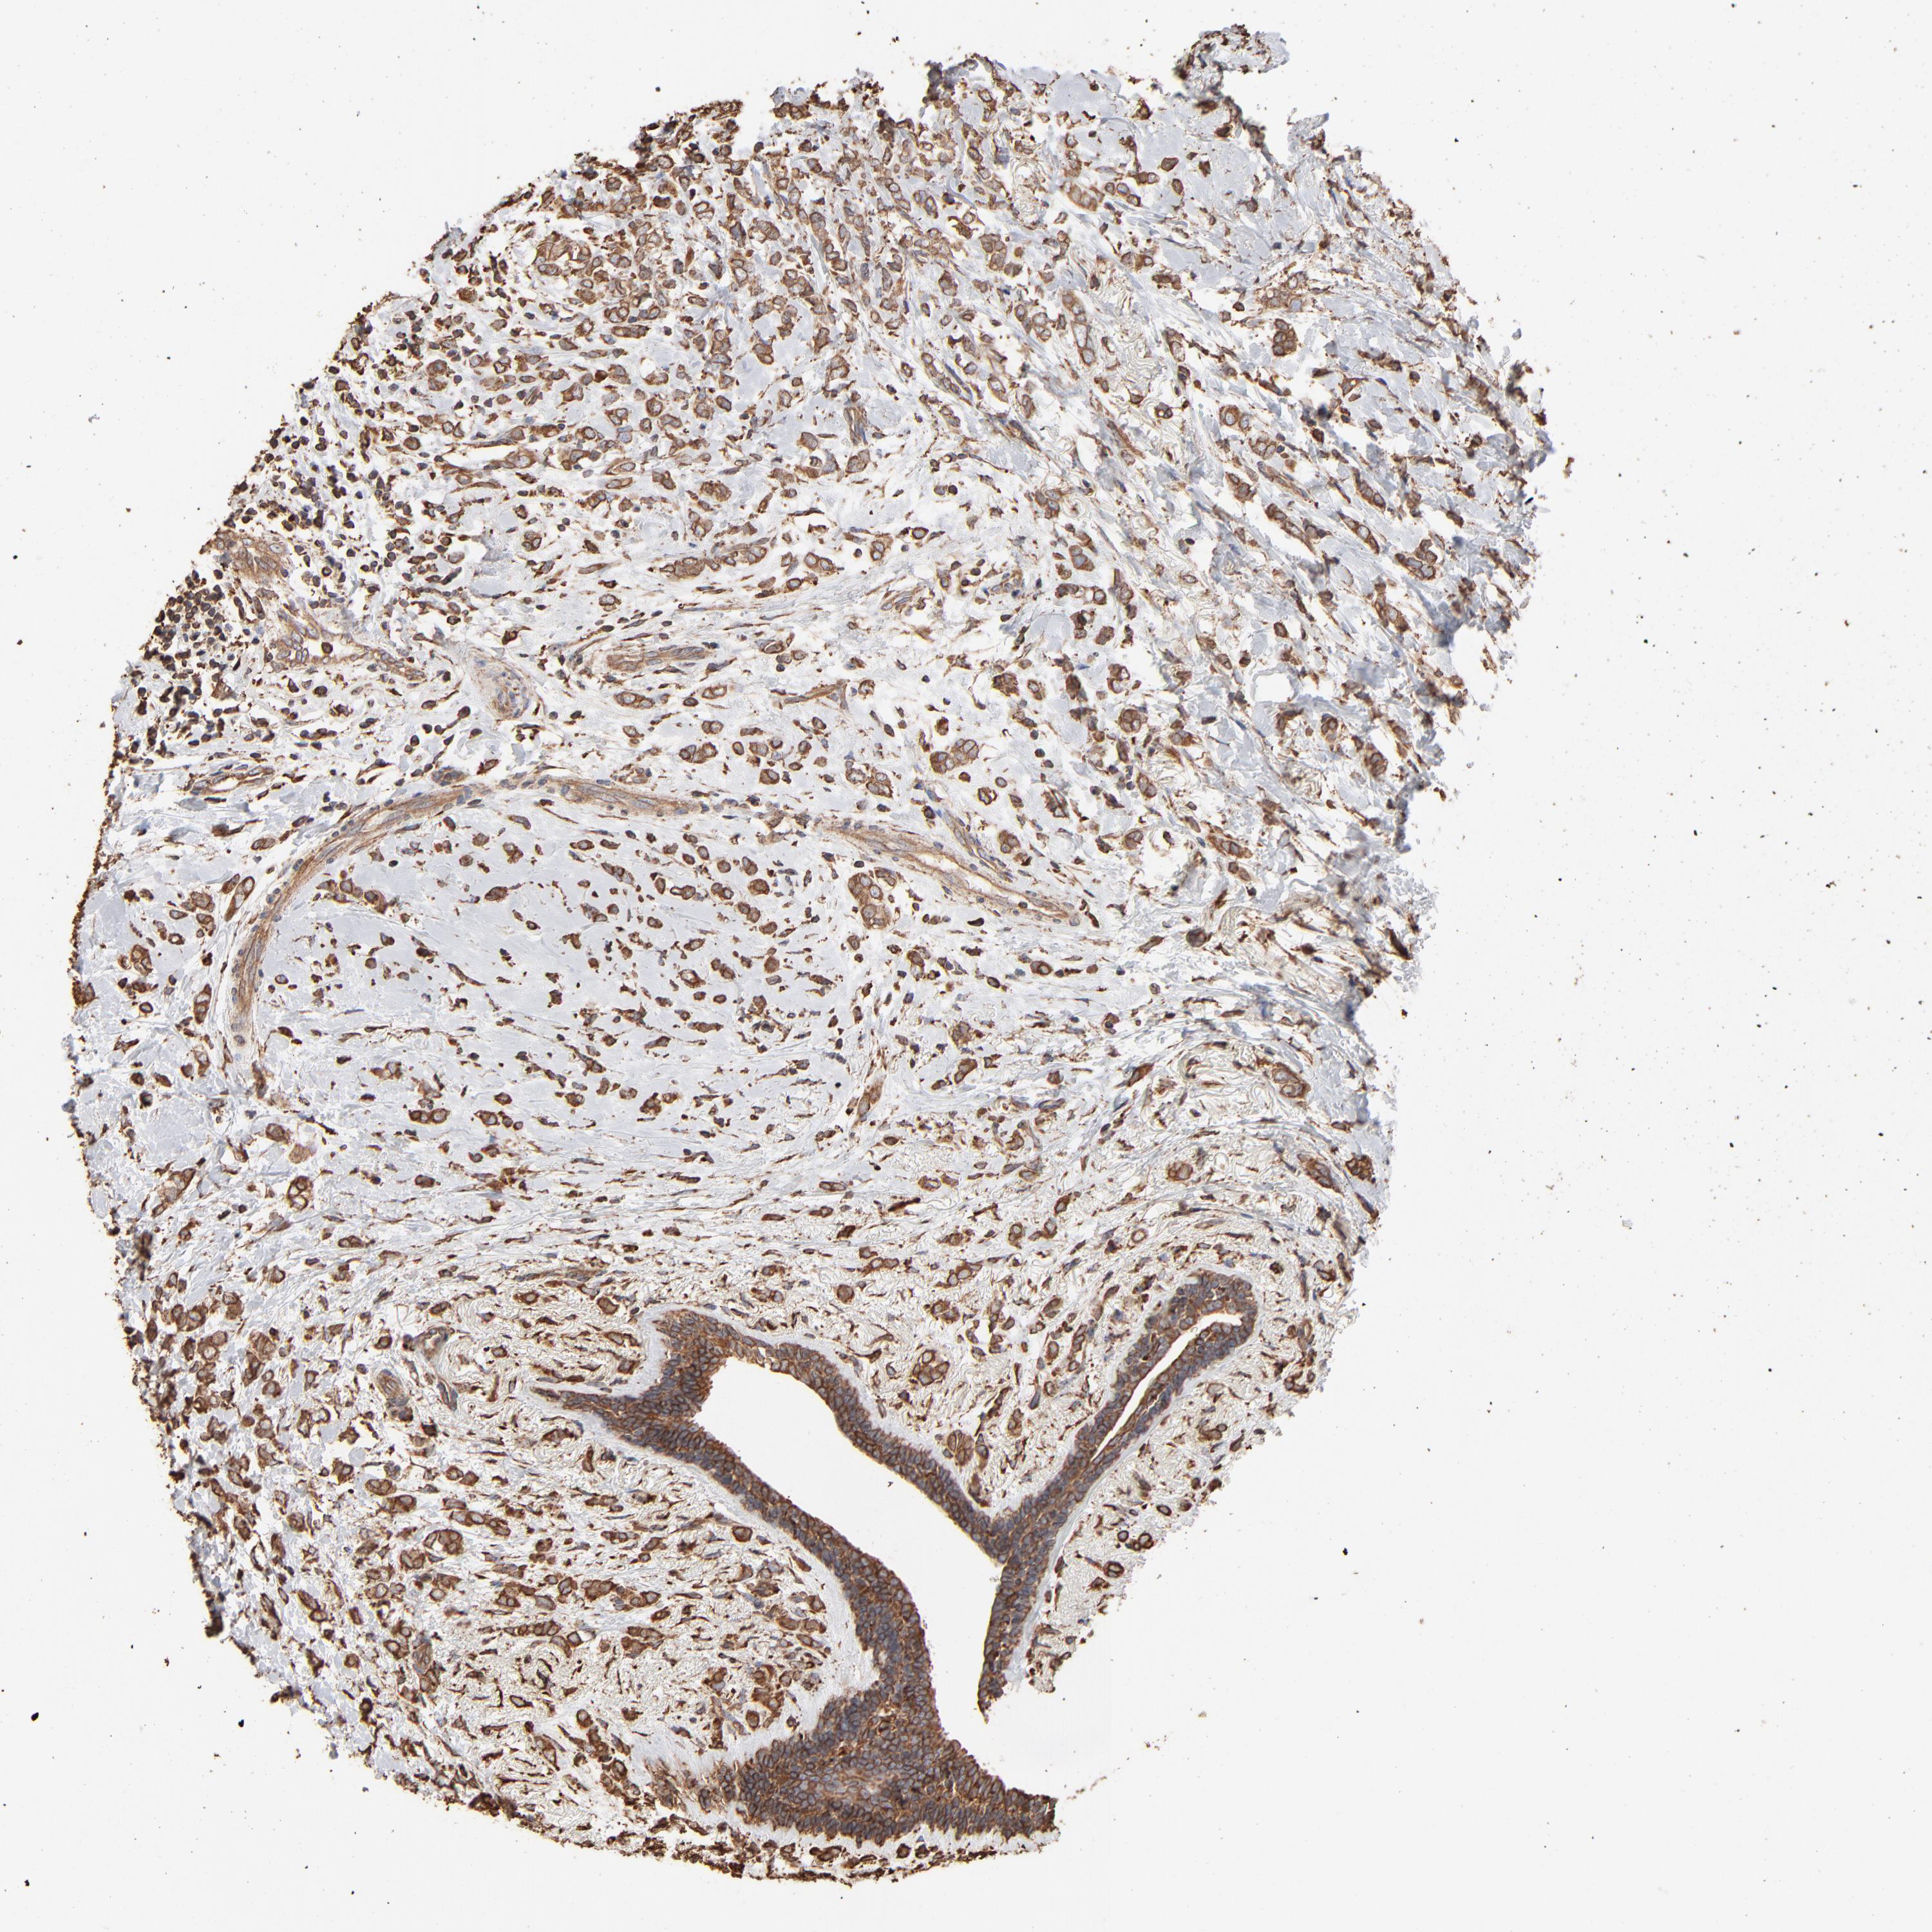

CANCER BREAST CANCER Show tissue menu

BRCA TCGA BRCA VALIDATION PROTEIN EXPRESSION